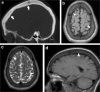

Calvarial lesions are often asymptomatic and are usually discovered incidentally during computed tomography or magnetic resonance imaging of the brain. Calvarial lesions can be benign or malignant. Although the majority of skull lesions are benign, it is important to be familiar with their imaging characteristics and to recognise those with malignant features where more aggressive management is needed. Clinical information such as the age of the patient, as well as the patient's history is fundamental in making the correct diagnosis. In this article, we will review the imaging features of both common and uncommon calvarial lesions, as well as mimics of these lesions found in clinical practice. TEACHING POINTS: • Skull lesions are usually discovered incidentally; they can be benign or malignant. • Metastases are the most frequent cause of skull lesions. • Metastatic lesions are most commonly due to breast cancer in adults and neuroblastoma in children. • Multiple myeloma presents as the classic "punched out" lytic lesions on radiographs. • Eosinophilic granuloma is an osteolytic lesion with bevelled edges.